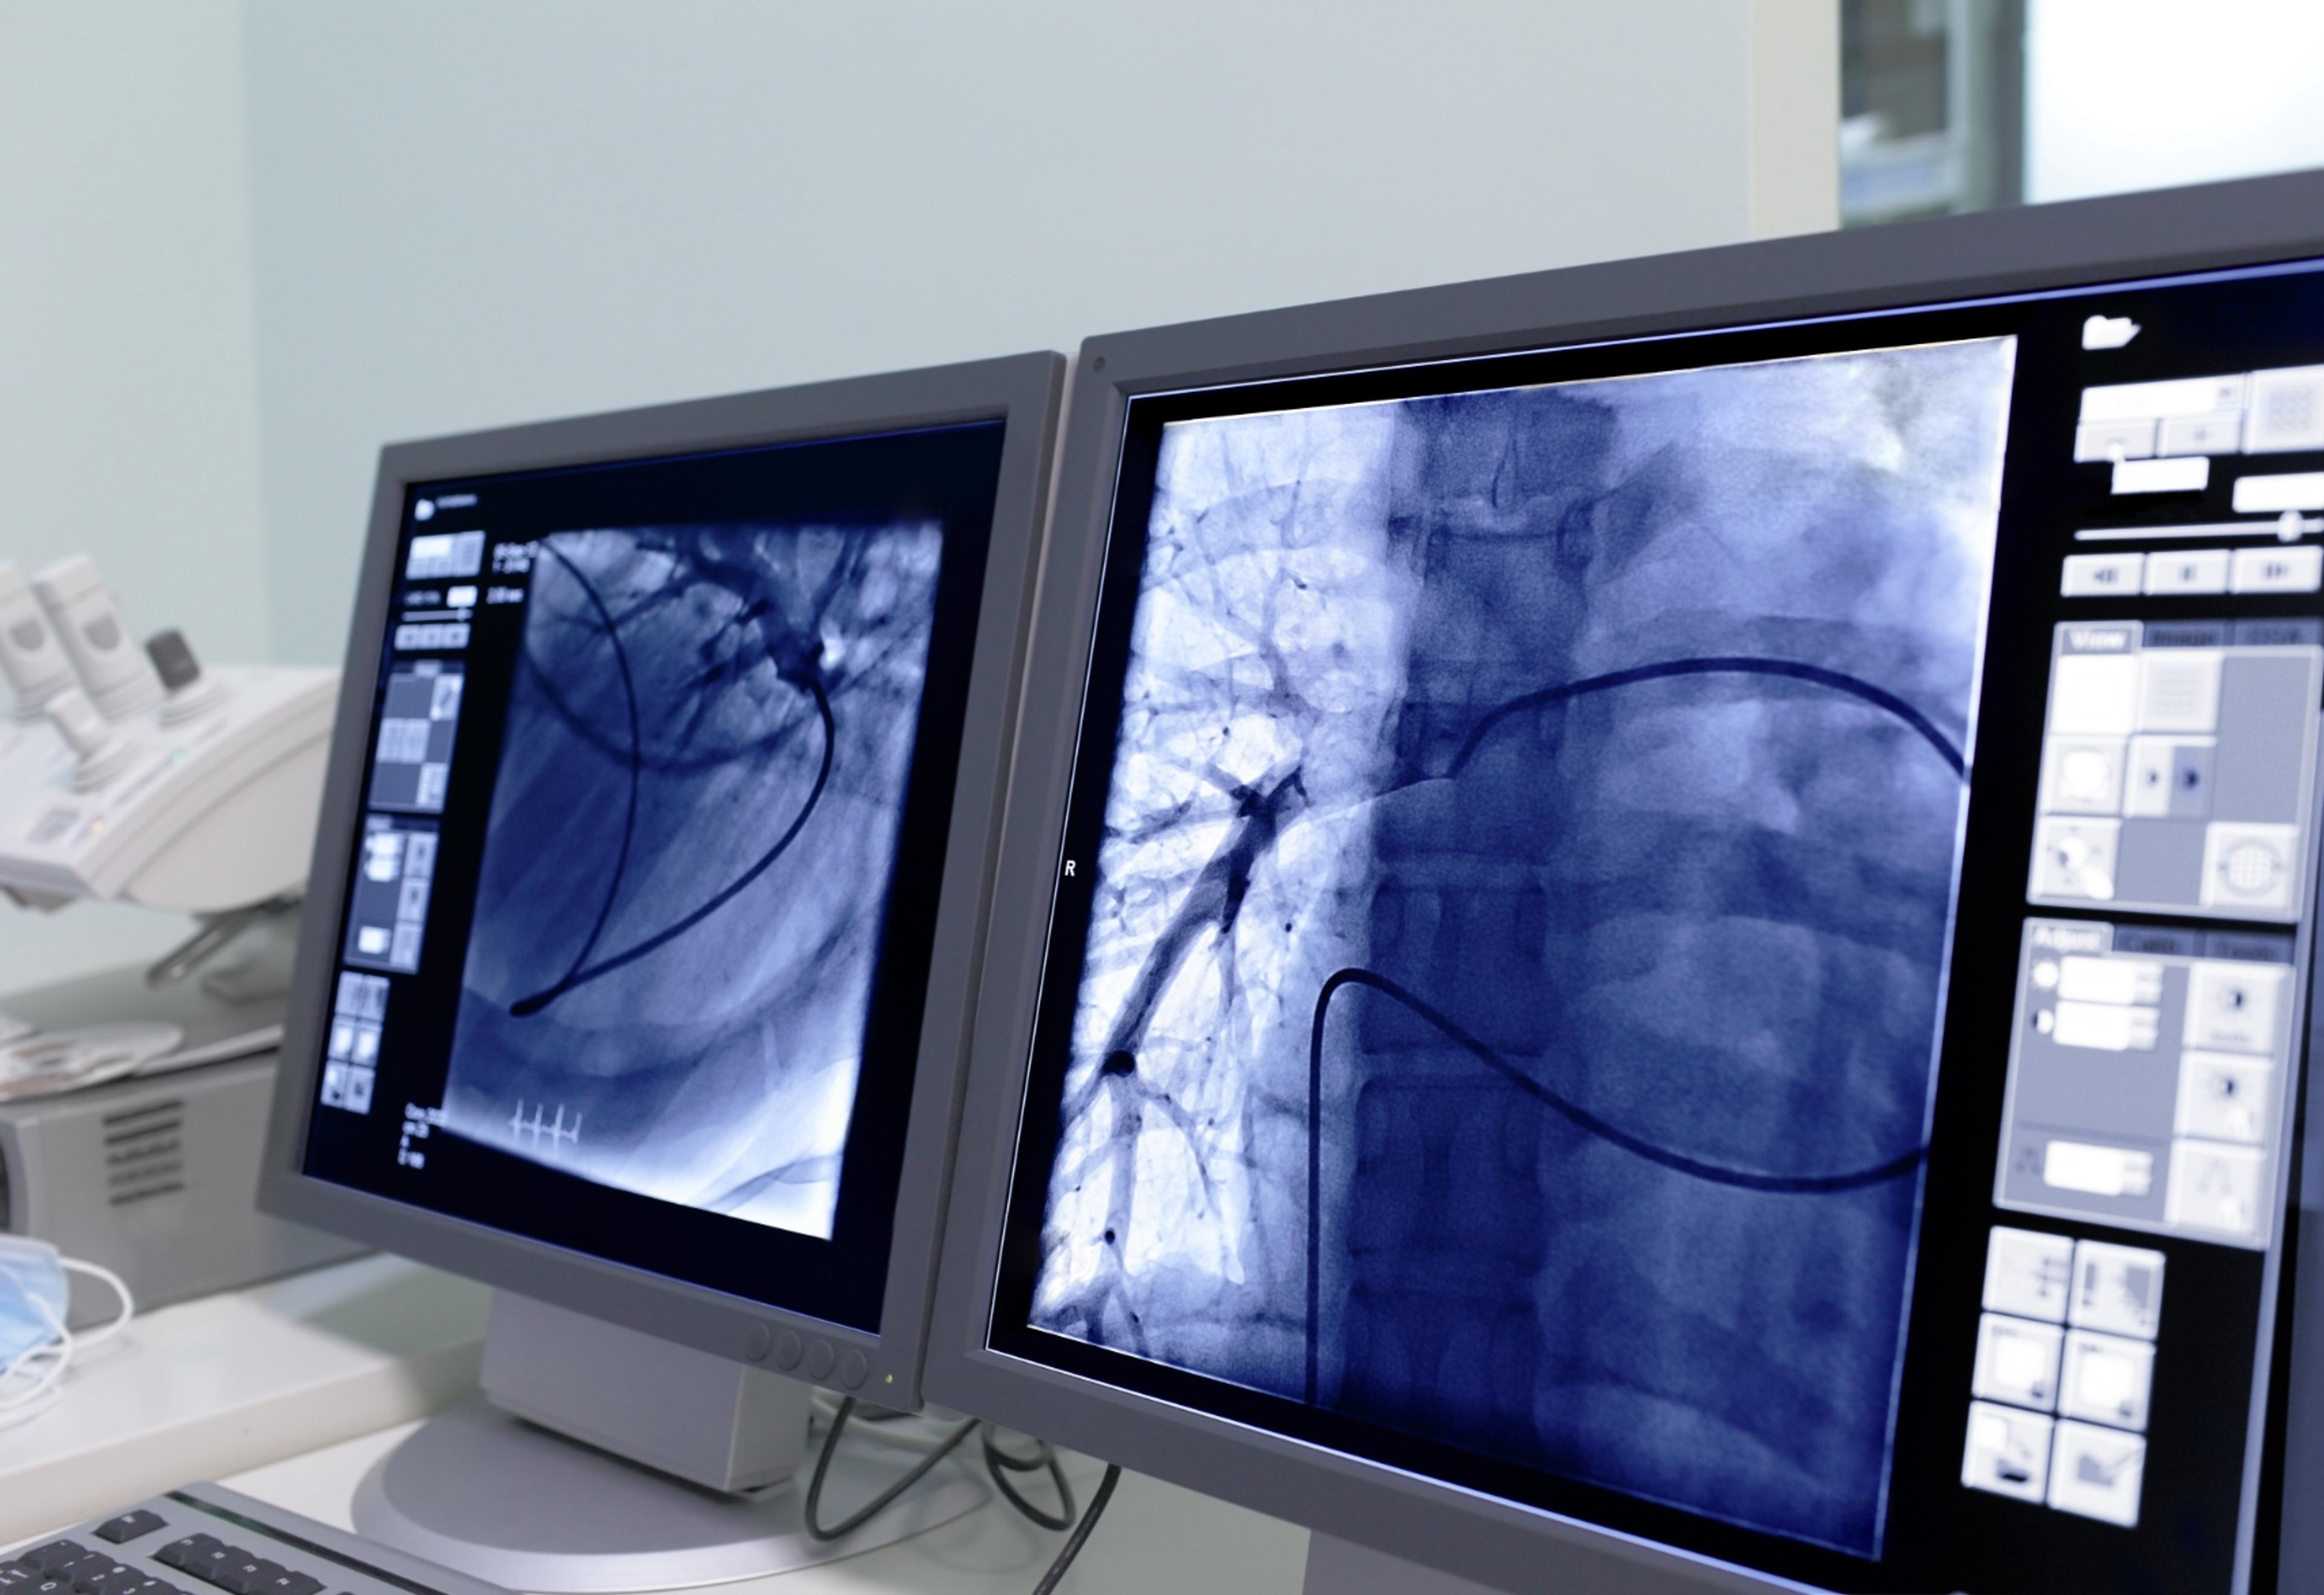

Catheter-directed thrombolysis is performed under imaging guidance. This procedure is designed to rapidly break up the clot, restore blood flow within the vein, and potentially preserve valve function to minimize the risk of post-thrombotic syndrome. Any narrowing in the vein that might lead to future clot formation can be identified by venography, an imaging study of the veins, and treated by the interventional radiologist with a balloon angioplasty or stent placement.

For patients whom thrombolysis and stenting is not appropriate and blood thinners are not medically appropriate, a vena cava filter may be inserted. IVC is a small device that functions like a catcher's mitt to capture blood clots, but allows normal liquid blood to pass.